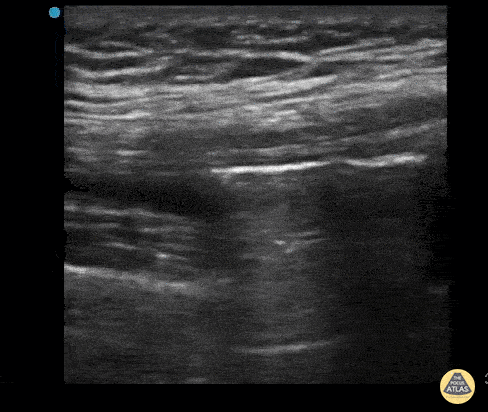

This is an ultrasound clip from a patient who presented to the ED after sustaining a laceration near the knee. There was concern for violation of the knee joint so ultrasound was used to evaluate. The probe is held in an sagittal orientation, just proximal to the patella, overlying the quadriceps tendon. A hyperechoic line with shadowing (similar in appearance to an A-line seen on lung US) can be seen deep to the quadriceps tendon confirming intra-articular air and therefore violation of the knee joint from the laceration. A small joint effusion can also be appreciated. Clip courtesy of Dr. Daniel Mantuani and Highland Ultrasound Twitter: @HGHED